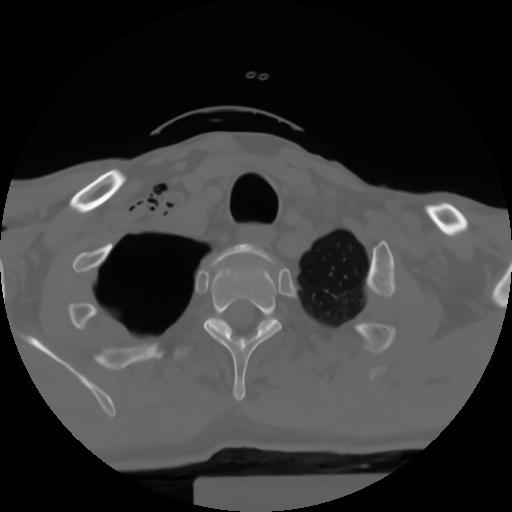

10 P.BLANDAS,,Axial,2.0,P.BLANDAS,,